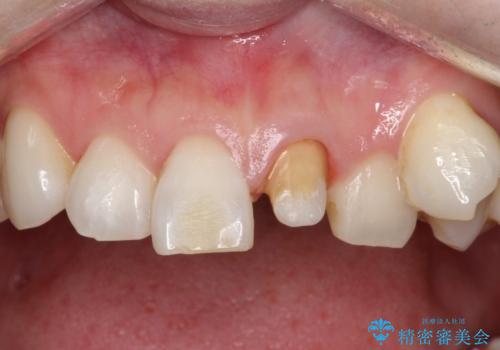

- 他院で前歯の変色をダイレクトボンディングにて修復治療しておりましたが、審美障害を主訴に来院されました。

根管治療後、オールセラミックにて治療を行っております。

ダイレクトボンディングはセラミックに比べ経年劣化しやすい材料です。

今回はオールセラミッククラウンによる治療を行いより審美的な修復ができました。